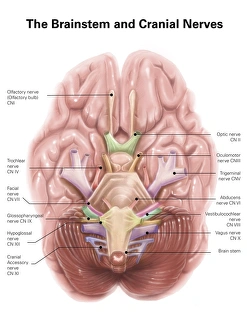

The central nervous system, the intricate network that governs our every thought and movement, is a marvel of complexity. From the delicate cerebellum tissue to the detailed light micrograph capturing its essence, we are reminded of its importance in maintaining balance and coordination. Anatomy comes alive as we explore the human brain from an inferior view. The intricacy of brain fibers is revealed through DTI MRI scans like C017/7099 and C017/7035, showcasing their vital role in transmitting information throughout this extraordinary organ. Artistic renderings bring us closer to understanding the medulla oblongata's significance within the brain. Its portrayal in various artworks allows us to appreciate how it controls essential functions such as breathing and heart rate. As we delve deeper into studying the central nervous system, models of the human brain provide invaluable insights into its structure and organization. Lateral views reveal countless regions responsible for cognition, emotion regulation, sensory perception, and motor control. Microscope slides offer glimpses into nerve cells' intricate architecture—a testament to their ability to transmit electrical signals at lightning speed. Meanwhile, glial stem cell cultures captured under a light microscope remind us of their crucial role in supporting neuronal function. Finally, artistic representations unveil the limbic system's enigmatic nature—an interconnected web responsible for emotions and memory formation. These captivating artworks allow us to visualize this complex network within our brains. Exploring these hints provides a glimpse into the awe-inspiring world of our central nervous system—the very foundation upon which our thoughts, actions, memories reside—reminding us just how remarkable our brains truly are.